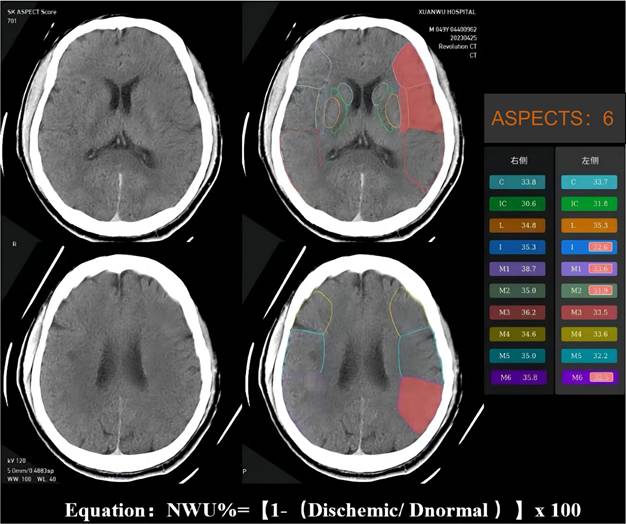

The NWU is an imaging index that uses the change in CT density (low attenuation) of ischemic brain tissue to quantify the severity of ischemic brain edema after stroke15. Ischemic brain tissue with marked hypoattenuation on NECT was confirmed visually. We used automated ASPECTS instead of CTP to assess the ischemic regions and calculate the NWU, which is more readily available and accessible. An automated software-based analysis (syngo. via Research Frontier, ASPECT Score-Tool v2.0.3; Siemens Healthineers) was used to calculate mean Hounsfeld unit (HU) values for ten regions of affected ASPECTS regions on non-contrast CT images and expressed as a percentage of the HU difference16. Using a predefined threshold for the relative HU difference, each ASPECTS region in the ischemic hemisphere was classified as affected (ischemic changes detected using software) or unaffected. The region of the ROI used to measure the density of ischemic (dischemic) and normal (normal) tissue was set between 20 and 80 Hu17. NWU% was calculated according to the following equation: NWU% = (1-Dischemic/Dnormal) ×100. The NWU% of the ischemic tissue was evaluated and validated by two experienced neuroradiologists (Figure 2).

Figure 2

Example for illustrating how the CT-ASPECTS-NWU% value was calculated. Density ischemic was 32.65 (the mean Density of ischemic ASPECTS regions [I, M1, M2, M6]). The Density normal was 36.2 (the mean HU of normal ASPECTS regions [I, M1, M2, M6]). The CT-ASPECTS-NWU% value was 9.81%.